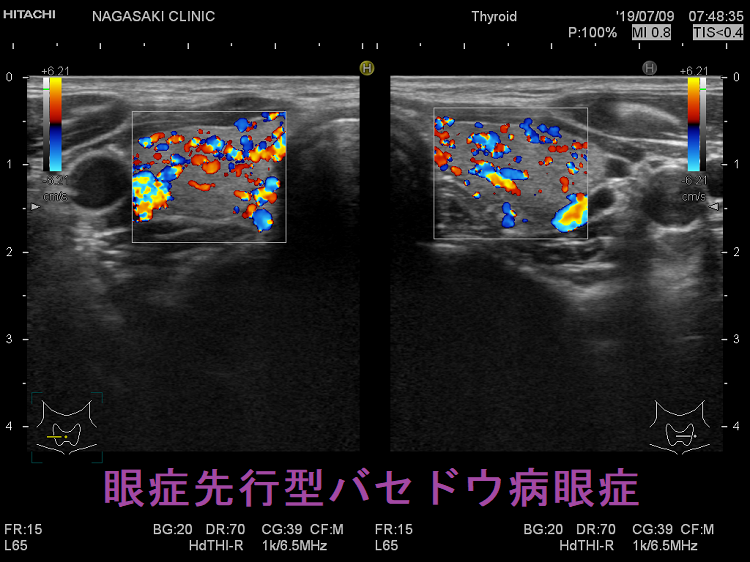

バセドウ病の約20%は、甲状腺ホルモンが高くなる前に眼症が先行します(眼症先行型バセドウ病眼症)。眼症先行型バセドウ病眼症は、甲状腺機能正常バセドウ病眼症より活動性が高いとされます。

甲状腺機能正常バセドウ病眼症は、眼症先行型バセドウ病眼症と異なります。伊藤病院の報告では

- 甲状腺機能正常だったバセドウ病眼症の24.1%は甲状腺機能亢進症に移行する(眼症先行型バセドウ病眼症)が72.4%はそのまま(甲状腺機能正常バセドウ病眼症)。

6.7年以上、甲状腺機能が正常だったバセドウ病眼症は、その後も甲状腺機能正常のまま(甲状腺機能正常バセドウ病眼症)の可能性が高い。[Clin Ophthalmol. 2018 Apr 19;12:739-746.]

- 眼症発症後3年以上甲状腺機能正常なものを甲状腺機能正常バセドウ病眼症、3 年以内に甲状腺機能亢進症に移行したものを眼症先行型バセドウ病眼症と定義すると、手術治療(眼筋、眼瞼)まで行う症例が、

- 甲状腺機能正常バセドウ病眼症 5.7%(2/35例)

- 眼症先行型バセドウ病眼症 60%(3/5例)

と、眼症の活動性に明確な差があったそうです。(第57回 日本甲状腺学会 P1-016 眼症先行型バセドウ病(PGD)とEuthyroid Graves’ Disease(EGD)の眼所見についての検討)